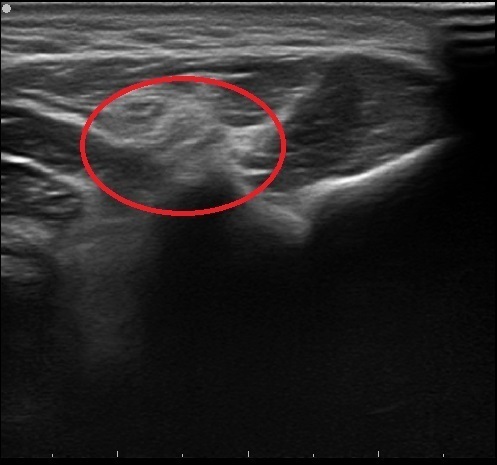

47歳 男性 両肘の痛み

当院来院時

左:患側

右:スタッフ健常者の肘

1週間前より両肘に痛み出現。

ベンチプレストレーニングをした翌日に痛み増悪するため、当院来院。

エコー観察にて関節内の水腫があると判断。

トレーニングを2週間休止するよう指示。